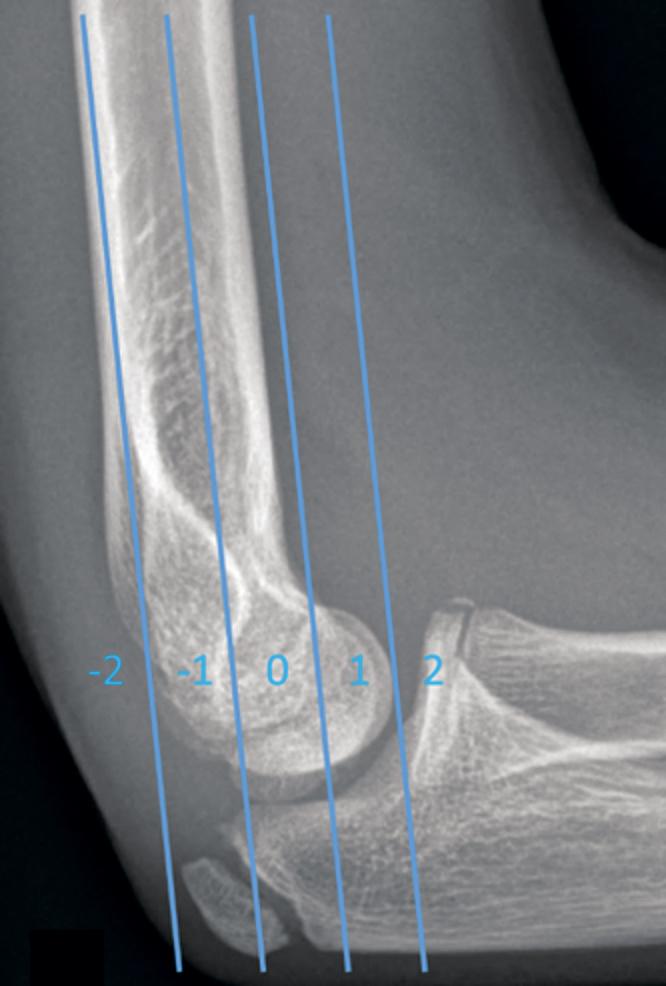

Background and purpose - The quality of pin fixation of displaced supracondylar humerus fractures in children has not been assessed, and the clinical value of radiographic examinations after pin fixation is unclear. We evaluated pin configuration, quality of osteosynthesis, and outcome in 264 supracondylar fractures. The clinical significance of postoperative radiographs was analyzed. Patients and methods - 252 Gartland-III and 12 flexion-type supracondylar humerus fractures were pin-fixed in the periods 2002-2006 and 2012-2014. During 2012-2014, staff were intructed that postoperative radiographs should not be taken. Quality of reduction was assessed by measuring Baumann and lateral capitellohumeral angles (LCHA) and also by recording the crossing point of the anterior humeral line (AHL) with bony capitellum. Rotatory alignment was registered as normal or abnormal. Pin configuration and quality of osteosynthesis were evaluated. The clinical significance of postoperative radiographs was analyzed. Results - Postoperatively, Baumann angle was normal in 66% of the fractures, AHL crossed the capitellum in 84%, and no malrotation was evident in 85% of the fractures. Crossed pins were used in 89% of the cases. 2 or more pins fixed both fracture fragments in 66%. Radiographic examinations were inadequate for assessment of LCHA in 13%, of Bauman angle in 8%, of AHL in 2%, of rotation in 1%, and of pin fixation in 2% of the cases. Postoperative radiographs did not give useful information except in 1 patient who had corrective osteotomy. All 94 patients with follow-up (97%) who were treated during 2012-2014 were satisfied with the outcome. Interpretation - Despite pin fixation being deemed unsatisfactory in one-third of the cases, significant malunion was rare. Postoperative radiography did not alter management or outcome.

背景与目的——儿童移位性肱骨髁上骨折的克氏针固定质量尚未得到评估,克氏针固定后影像学检查的临床价值也不明确。我们评估了264例肱骨髁上骨折的克氏针构型、骨接合质量及预后情况,并分析了术后X线片的临床意义。患者与方法——252例Gartland-III型和12例屈曲型肱骨髁上骨折于2002年至2006年及2012年至2014年期间采用克氏针固定。在2012年至2014年期间,工作人员接到指示,术后不应拍摄X线片。通过测量鲍曼角和肱骨头外侧角(LCHA)以及记录肱骨前线(AHL)与肱骨小头的交叉点来评估复位质量。旋转对线记录为正常或异常。评估克氏针构型和骨接合质量,并分析术后X线片的临床意义。结果——术后,66%的骨折鲍曼角正常,84%的骨折AHL穿过肱骨小头,85%的骨折无明显旋转畸形。89%的病例使用了交叉克氏针。66%的病例用2根或更多克氏针固定骨折碎片。在13%的病例中,X线检查不足以评估LCHA,8%的病例中不足以评估鲍曼角,2%的病例中不足以评估AHL,1%的病例中不足以评估旋转情况,2%的病例中不足以评估克氏针固定情况。除1例行截骨矫正术的患者外,术后X线片未提供有用信息。2012年至2014年期间接受治疗的所有94例有随访记录(97%)的患者对预后满意。解读——尽管三分之一的病例中克氏针固定被认为不令人满意,但严重畸形愈合很少见。术后X线检查并未改变治疗方案或预后。